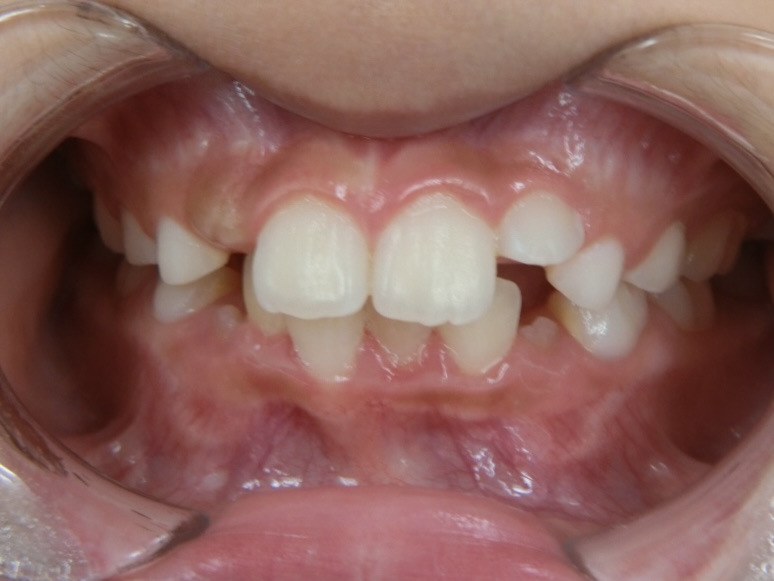

Before 1

8歳女児 ガタガタが気になる

8歳女の子の症例です。

永久歯の萌出スペースが不足しており、ガタガタの歯並びを気にされてご来院されました。

「目立たない装置で治療したい」とのご希望で、子ども用インビザラインで治療を行いました。

1年3ヶ月の治療で、きれいな歯並びへと改善しました。

施術内容 インビザラインファースト

治療期間 1年3ヶ月